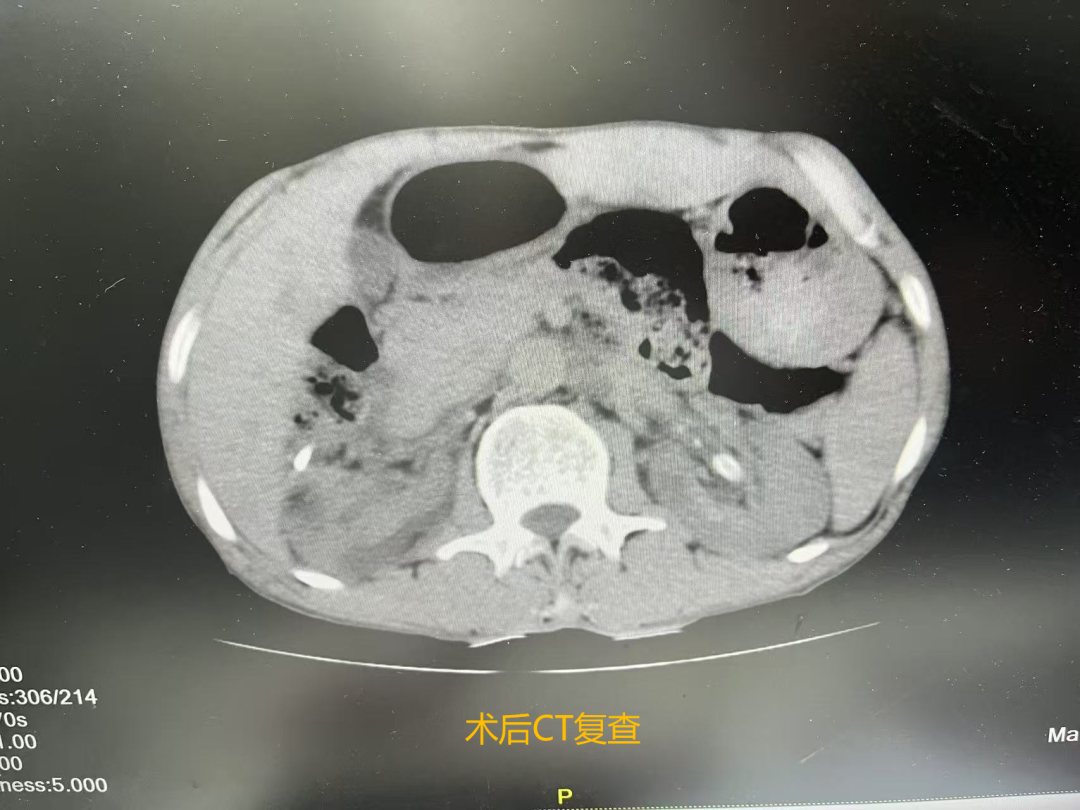

次日复查泌尿系CT示:左侧肾盂-输尿管移行处结石已完全清除,未见肾脏积液及血肿达到了一次彻底清石的效果。目前,患者正在康复治疗中。